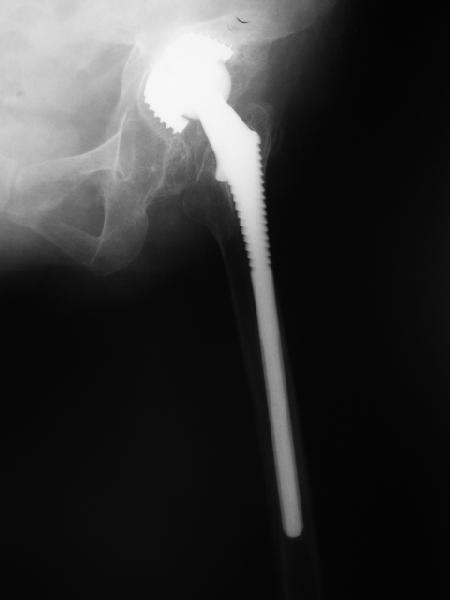

Август 2002 г.

24 апреля 2005 г. правый сустав профиль (тут и болит)